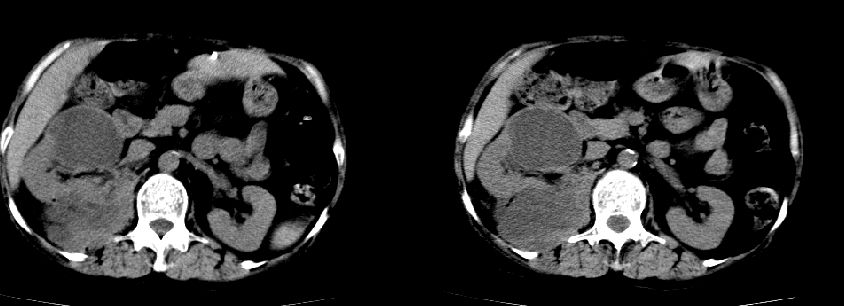

以下是引用liuyue在2008-7-19 10:17:00的发言:[br]考虑:1.肾周脓肿,肾实质、腰大肌及侧腹壁均受累及。 2.右肾囊肿。[br]建议:强化扫描,除外肾癌之可能。[br]

以下是引用zhengfaming在2008-7-19 14:48:00的发言:[br]右肾脓肿并感染可能性大,建议增强

以下是引用江广1996在2008-7-19 10:48:00的发言:[br]先考虑右侧肾周感染脓肿形成并累及腰大肌,右肾前侧有病灶考虑囊肿。